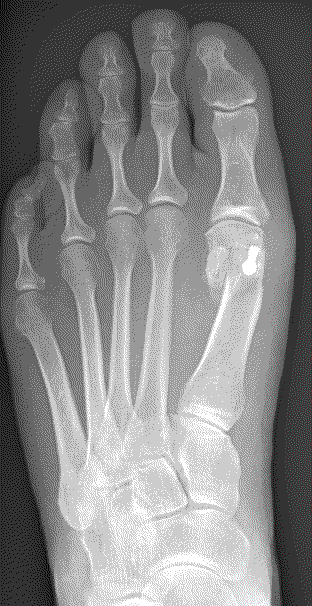

The severity of the condition is assessed by an X-ray. There is no direct correlation between the size of the deformity and the degree of symptoms experienced.

Capital osteotomy

This is an osteotomy in the metatarsal head (transposition), the metatarsal head is moved to correct the deformity and fixated with a single screw. It is indicated for mild to moderate deformities. The choice to carry out a Scarf or a capital osteotomy will be made by your consultant.

Scarf osteotomy

This is a transposition osteotomy. It is normally indicated for mild to moderate deformities. The new position of the first metatarsal is maintained with two screws which enables stability.